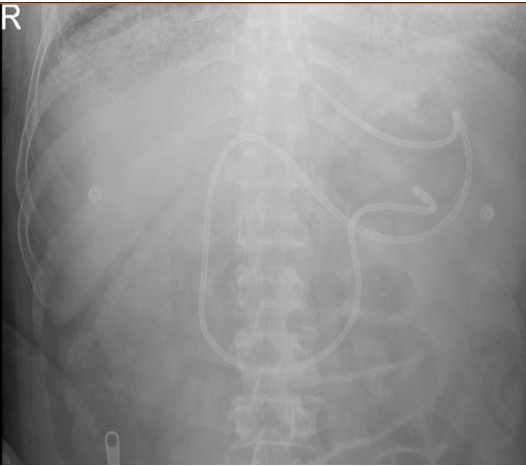

3. 置管后位置判断

腹部平片是判断鼻肠管末端位置的“金标准”。鼻肠管留置成功的腹部平片主要具有以下特征:①鼻肠管在腹部呈“左-右-左”的走势,并伴有螺旋式下降;②在脊柱右侧形成十二指肠环,呈“C”形且导管下降高度>2个锥体;③导管远端位于左下腹,远离胃腔轮廓之外图4[2]

图片

图4  鼻肠管腹部平片